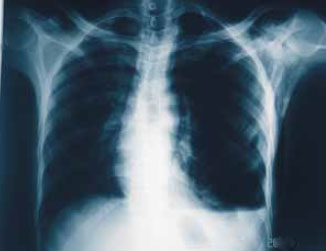

Диагностировать напряженный пневмоторакс по чисто клиническим показателям трудно, за исключением случая явной дыхательной недостаточности, когда не следует терять время на рентгенографию (рис. 2; также см статьи «Рентгенография: Травмы грудной клетки. Пневмоторакс. Пневмомедиастинум» и «Рентгенологический атлас: Травмы Грудной Клетки»). Это состояние требует немедленного введения канюли большого диаметра для венепункции во втором или третьем межреберье по среднеключичной линии (плевральная пункция), подсоединенной в качестве временной меры к одностороннему клапану Геймлиха, сделанному из подручных материалов (рисунок 3). Несомненным показателем пневмоторакса является внезапный прорыв воздуха, когда игла входит в плевральную полость. Канюля должна быть достаточно длинной (8 см) для того, чтобы полностью пройти сквозь мышцы стенки грудной клетки (толщина которой в среднем составляет 4–6 см). Плевральную пункцию необходимо как можно скорее заменить межреберной плевральной дренажной трубкой (установленной по среднеключичной линии или в пятом межреберье по переднеподмышечной линии).

Рисунок 2. Напряженный пневмоторакс с дыхательной недостаточностью. В данном случае диагностировать состояние можно было по клиническим показателям.